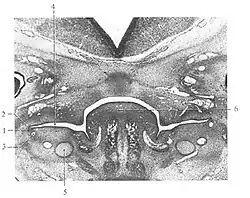

Bei 11 bis 15 mm großen menschlichen Embryonen beginnt die Entwicklung des juxtaoralen Organs als Aussprossung einer Epithelleiste (1) aus dem Mundhöhlenepithel einer Seitentasche (Sulcus buccalis) der embryonalen Mundhöhle. In der Folge verlagert sich die Organanlage zusammen mit dem Nerven weg von der Mundschleimhaut an die eingangs erwähnte Stelle der tiefen Gesichtsregion.